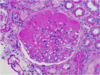

What is shown here? What’s the big black glob in the middle?

another glomerulus

big black glob is the nuclei of the mesangial cells. Lays down matrix in the middle there.